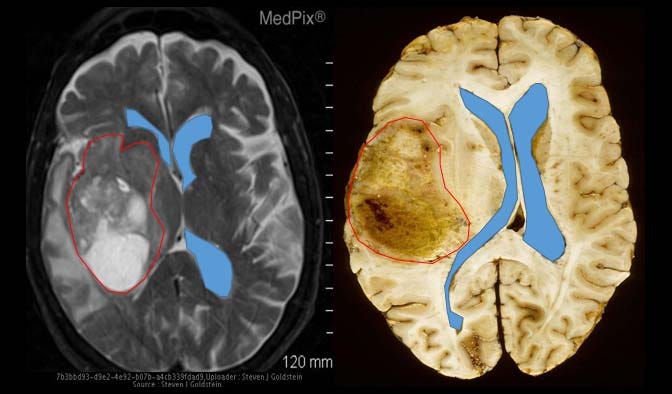

Here is an image of a normal, healthy brain. Pay close attention to the white structure in the middle:

And here are examples of two similar patients with glioblastoma. Notice how those two blue lines (representing the cerebral ventricles), which should normally be symmetrical along the middle of the brain, have been either pushed to the side or compressed by the red outline, representative of a glioblastoma tumor.

Imagine that you are a patient and you just received an MRI scan showing similar results as above.

You’ve just received a death sentence: a glioblastoma tumor diagnosis.